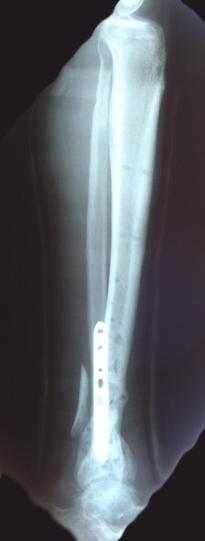

Post-corrective surgery X-Rays of the damaged right & left legs / ankles

The first two x-rays show Liam’s left ankle and pelvis prior to the accident. For comparison purposes it is interesting to see the

differences. The next x-rays were taken after the corrective surgery performed by Dr. Armendariz. Noticed that Dr. Armendariz has used tibia

bracing and also aligned the bone fragments of the left leg so that they could heal in the proper orientation. The external fixation has been

removed and Liam’s left foot has been returned to a more natural alignment.